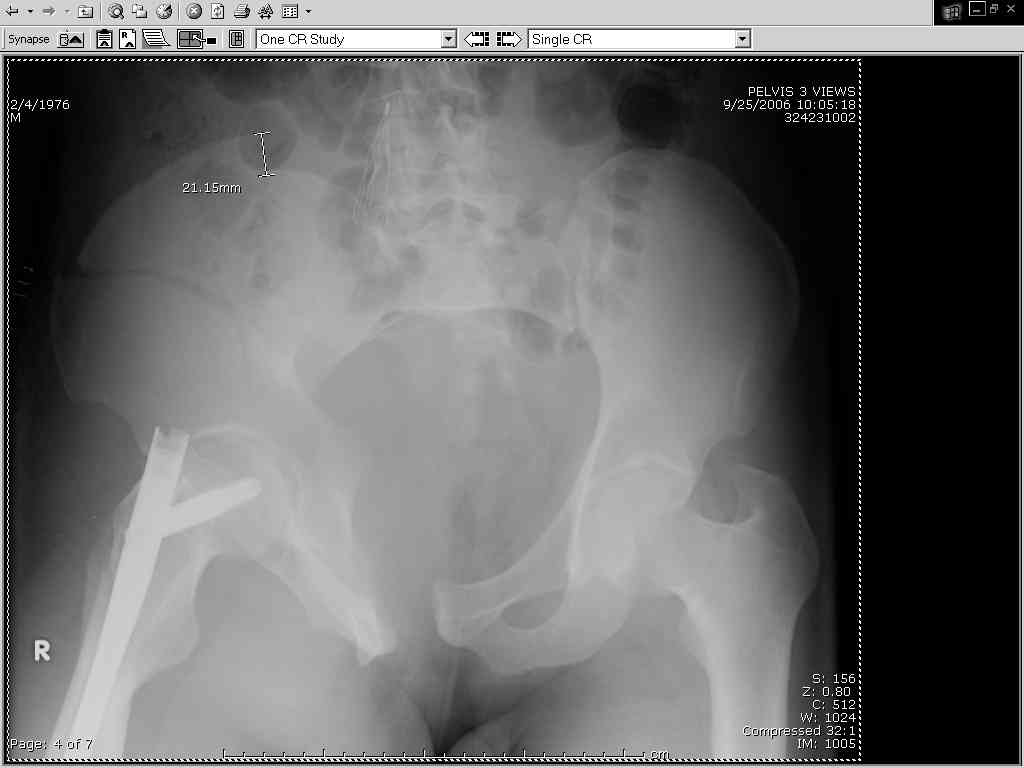

Thanks Adam - I agree it's not a pure APC (is there really such thing as a pure force vector strictly in the x,y or z plane?). I stand corrected. Maybe a hybrid APC (ext rot of L hemipelvis, symphysis disruption, ext rot of R anterior innominate) plus vertical shear as well with 3 or-so cm of cephalad migration of the R ilium. Maybe just "C-type".....

It almost looks to me like an extra-articular both column fx, in addition to the pelvic component. It has the typical triangular fragment and the OO view has a hint of the spur. You may be able to get it all with plates. I would consider fixing the crest first, then a long plate for both symph and iliac portion. SI may close with reduction of symphisis. Looks like the inferior portions are intact. I like your plan as well. You will probably solicit lots of opinion. Good luck. Look forward to post op view.